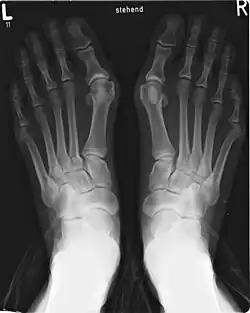

Een hallux valgus kan worden gediagnosticeerd en geanalyseerd met een eenvoudige röntgenfoto, die moet worden genomen met het gewicht op de voet. De hallux valgus hoek (HVA) is de hoek tussen de lange assen van de proximale falanx en het eerste middenvoetsbeen van de grote teen. Het wordt als abnormaal beschouwd als het groter is dan 15-18°. De volgende HV hoeken kunnen ook worden gebruikt om de ernst van de hallux valgus te bepalen[1]:

- Licht: 15–20°

- Matig: 21–39°

- Ernstig: ≥ 40°

De intermetatarsale hoek (IMA) is de hoek tussen de lengteassen van het eerste en tweede middenvoetsbeen en is normaal gesproken minder dan 9°. De IM hoek kan ook de ernst van de hallux valgus aangeven als:

- Licht: 9–11°

- Matig: 12–17°

- Ernstig: ≥ 18°